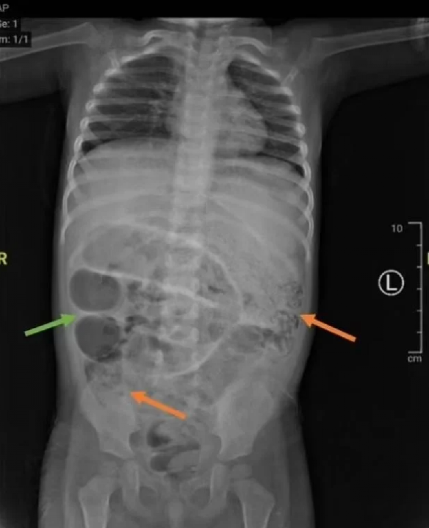

Dijagnoza je, prema rečima medicinskog osoblja, u početku bila blokada creva.

Tokom operacije, lekari su identifikovali i uklonili brojne crve Ascaris lumbricoides , dugačke nekoliko centimetara, koji su stvorili "gužvu" u tankom crevu deteta.

- Rez napravljen za uklanjanje parazita napravljen je na tački otprilike 50 centimetara od debelog creva. Crvi su poslati na dalju analizu u laboratoriju. Istovremeno, analize krvi su pokazale da dete boluje i od anemije, česte pojave u ovakvim slučajevima. Paraziti apsorbuju značajan deo gvožđa i drugih hranljivih materija u telu, uzrokujući, između ostalog, probleme u razvoju deteta. Mladom pacijentu je određena terapija antibioticima, hidratantnim rastvorima i preparatima protiv crevnih parazita. Otpušten je nedelju dana kasnije - prenose mediji.